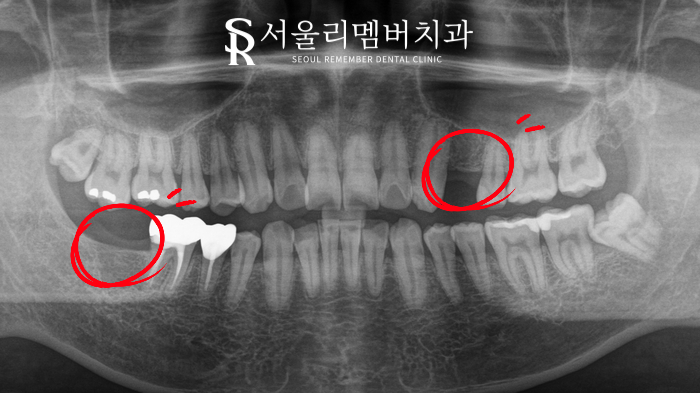

치료 전

이 환자분의 경우,

전에 치료받은 곳에서 좋지 않은 경험을 하여

많이 무서워하셨습니다.

콕콕 쑤시며 아프다는 주소와 함께

신길동 치과 에 내원해 주신 날,

치아 두 개의 상태가 많이 안 좋아 보였습니다.

제대로 확인해 보기 위해

파노라마를 촬영해 보았는데요.

이미 자연치 두곳이 상실되어

빠져있는 것이 관찰되었습니다.